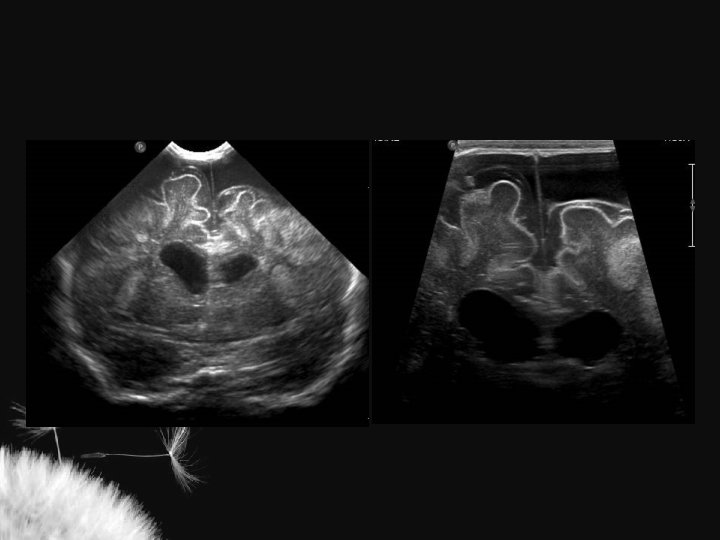

VENTRICULOMEGALIA

Considerações IR = S – D S Perfusão Q = A x TAV Aumento da PIC 1. Aumento da velocidade sistólica 2. Diminuição da velocidade diastólica Compressão fontanelar 1. Normal – aumenta até 6% 2. Diminuição da complacência craniana – > = 20%

Condições extracranianas que alteram o IR Fator Aumento do p. CO 2 Aumento da FC PCA Pneumotórax Isquemia miocárdica Policitemia Anemia Indometacina Surfactante IR